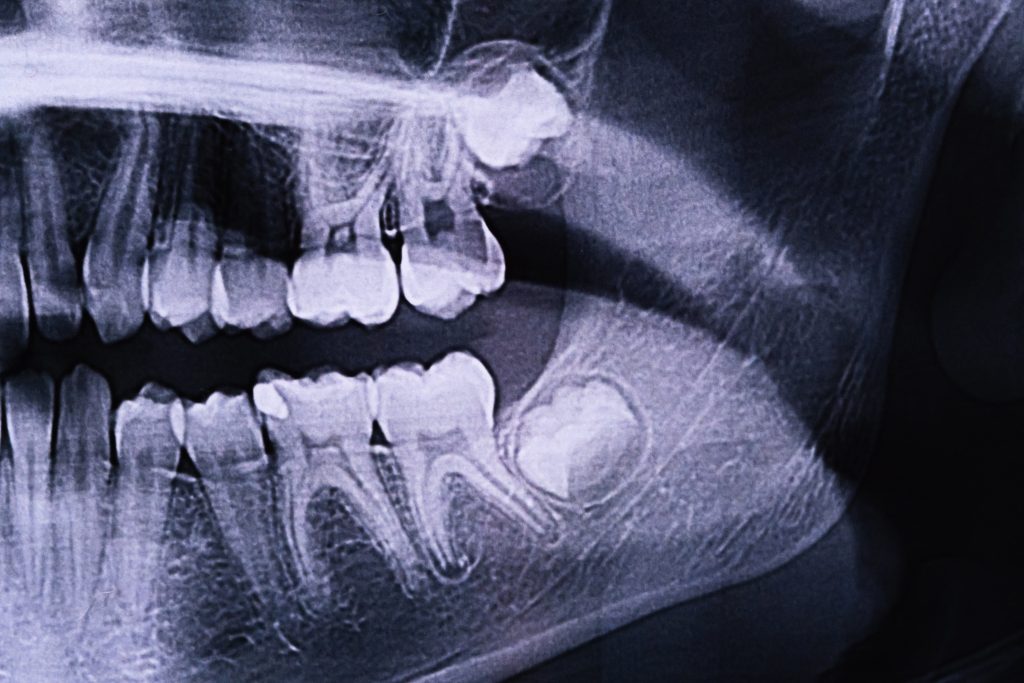

Las muelas del juicio son los terceros molares, que suelen erupcionar entre los 17 y los 25 años. En muchos casos, estas piezas no encuentran el espacio adecuado para salir correctamente, lo que da lugar a una erupción parcial o una inclusión dentaria (cuando quedan retenidas dentro del hueso o la encía). Esta situación puede derivar en infecciones, quistes, caries en los dientes adyacentes, o incluso en problemas ortodóncicos.

- Impactación dental, cuando la muela crece en ángulo o no erupciona por falta de espacio.

- Evaluación preoperatoria con radiografía panorámica o escáner CBCT.